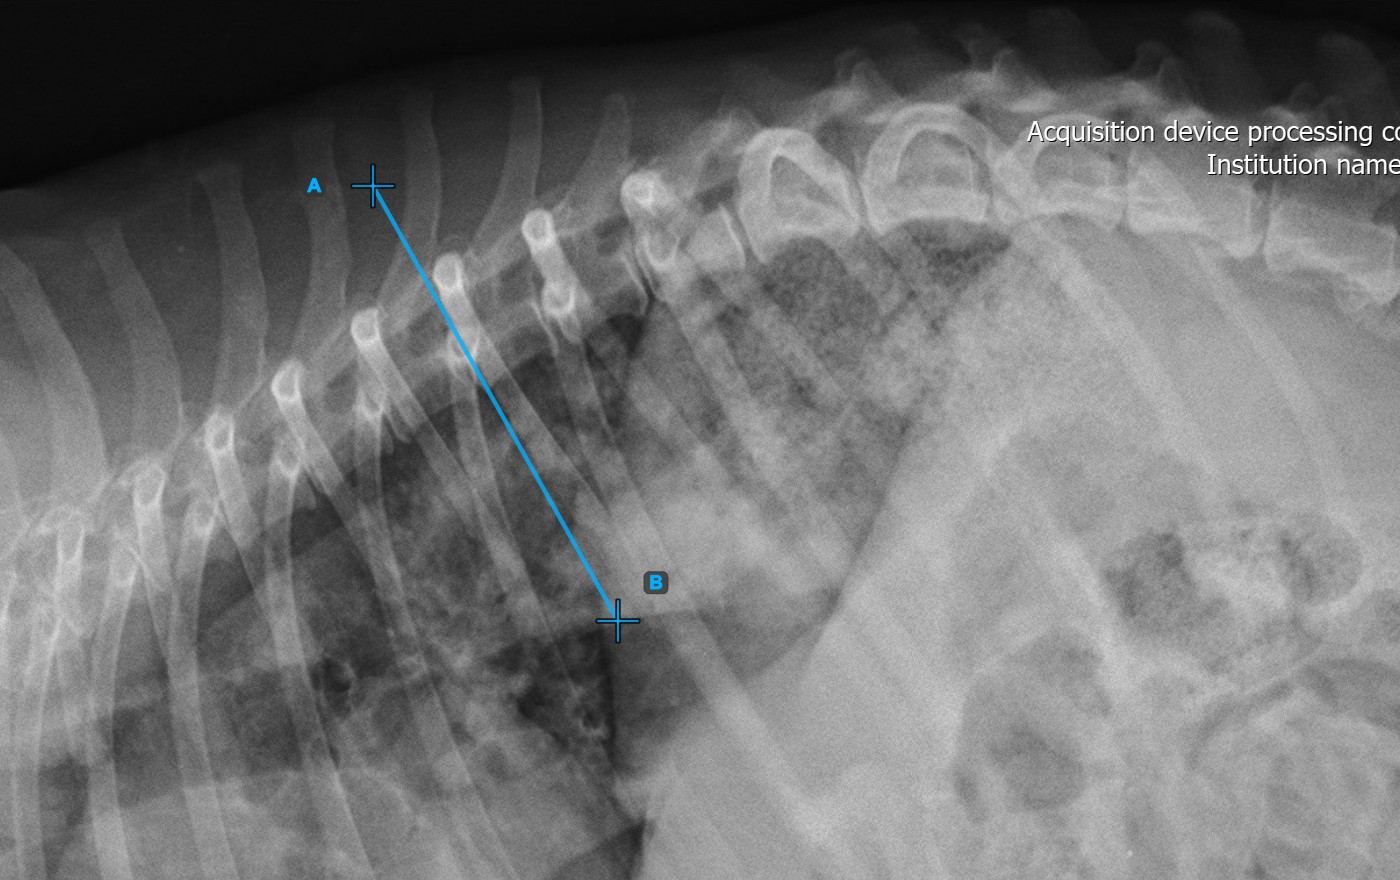

Identify the vertebral endplate at the initial point of the largest spinal curve deformity. Place the start and end point of the first vertebral line precisely along the identified endplate. Adjust each point on the scene to better align the line with the endplate if needed.

The image below represents a typical placement of the first vertebral line.